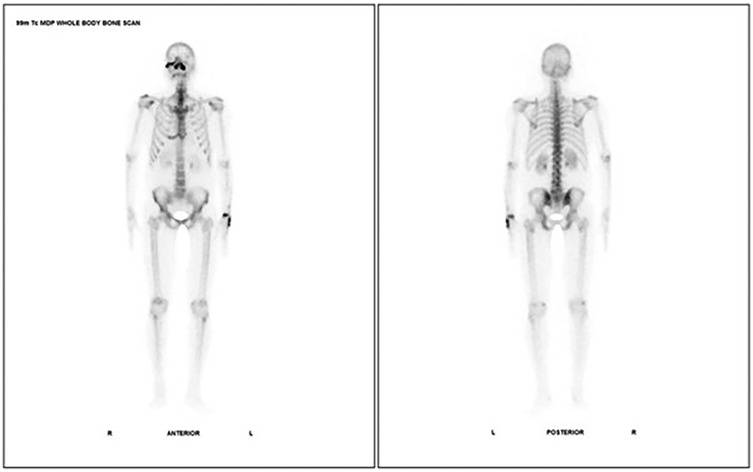

A Case series of 99mTc-MDP Bone Scintigraphy (Planar and SPECT CT) in Mucormycosis IN THE ERA OF COVID 19

Mucormycosis is a serious fungal infection affecting immunocompromised individuals, caused by fungi from the Mucorales order, particularly Rhizopus species. It primarily spreads through inhalation of spores, with diabetes, cancers, organ transplants, immunosuppressive drugs, and COVID-19 being major risk factors. The infection manifests in various forms such as encephalic, cutaneous, gastrointestinal, pulmonary, and rhino cerebral, often leading to tissue necrosis and blood vessel invasion. Imaging diagnosis is aided by CT and MRI scans, while 99m Tc MDP bone scintigraphy has found to be a more accurate imaging tool to look for bone remodelling and erosive changes associated with invasive fungal sinusitis including mucormycosis. Treatment involves prompt surgical debridement and addressing the underlying immune deficiency. Here we present a series of cases where 99m Tc MDP bone scintigraphy played a key role in management of mucormycosis of the head. In conclusion, 99mTc MDP scintigraphy is a promising tool for evaluation, guiding diagnosis and management of mucormycosis.